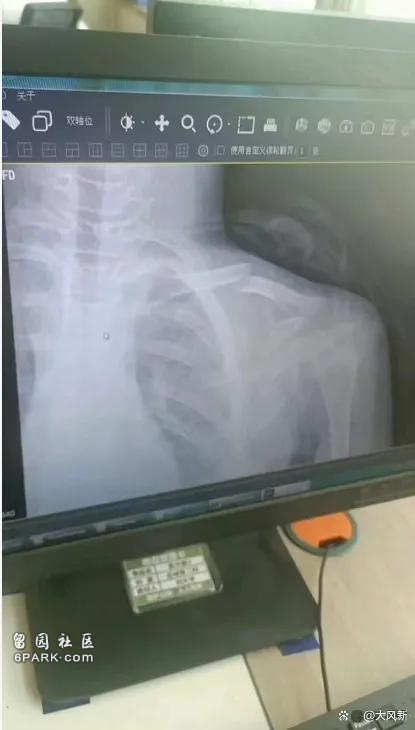

学生体胖跳绳慢被体育老师踹断锁骨?警方:已立案

学生体胖跳绳慢被体育老师踹断锁骨?警方:已立案 我们的赞助商 评论 发表评论 相关功能 新闻